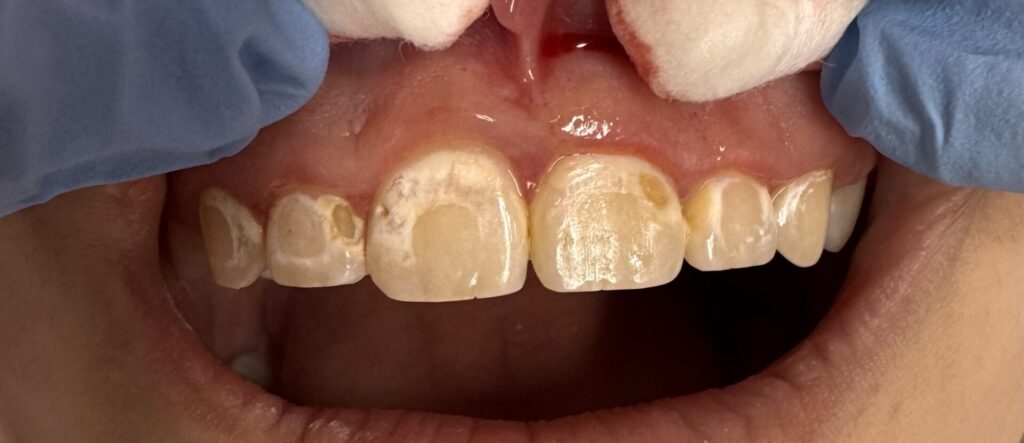

The Challenge The patient arrived at Serenity Dental Spa with a single, pronounced source of self-consciousness: a discolored and noticeable composite filling on a prominent